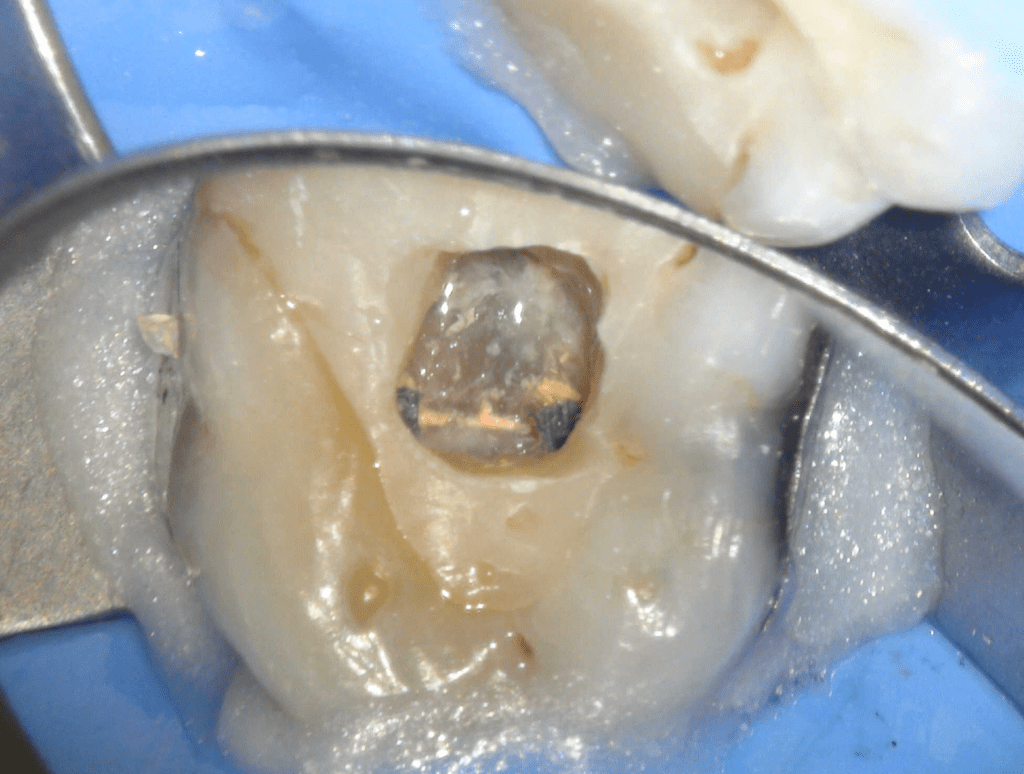

Fisura, remoción amalgama para explorar